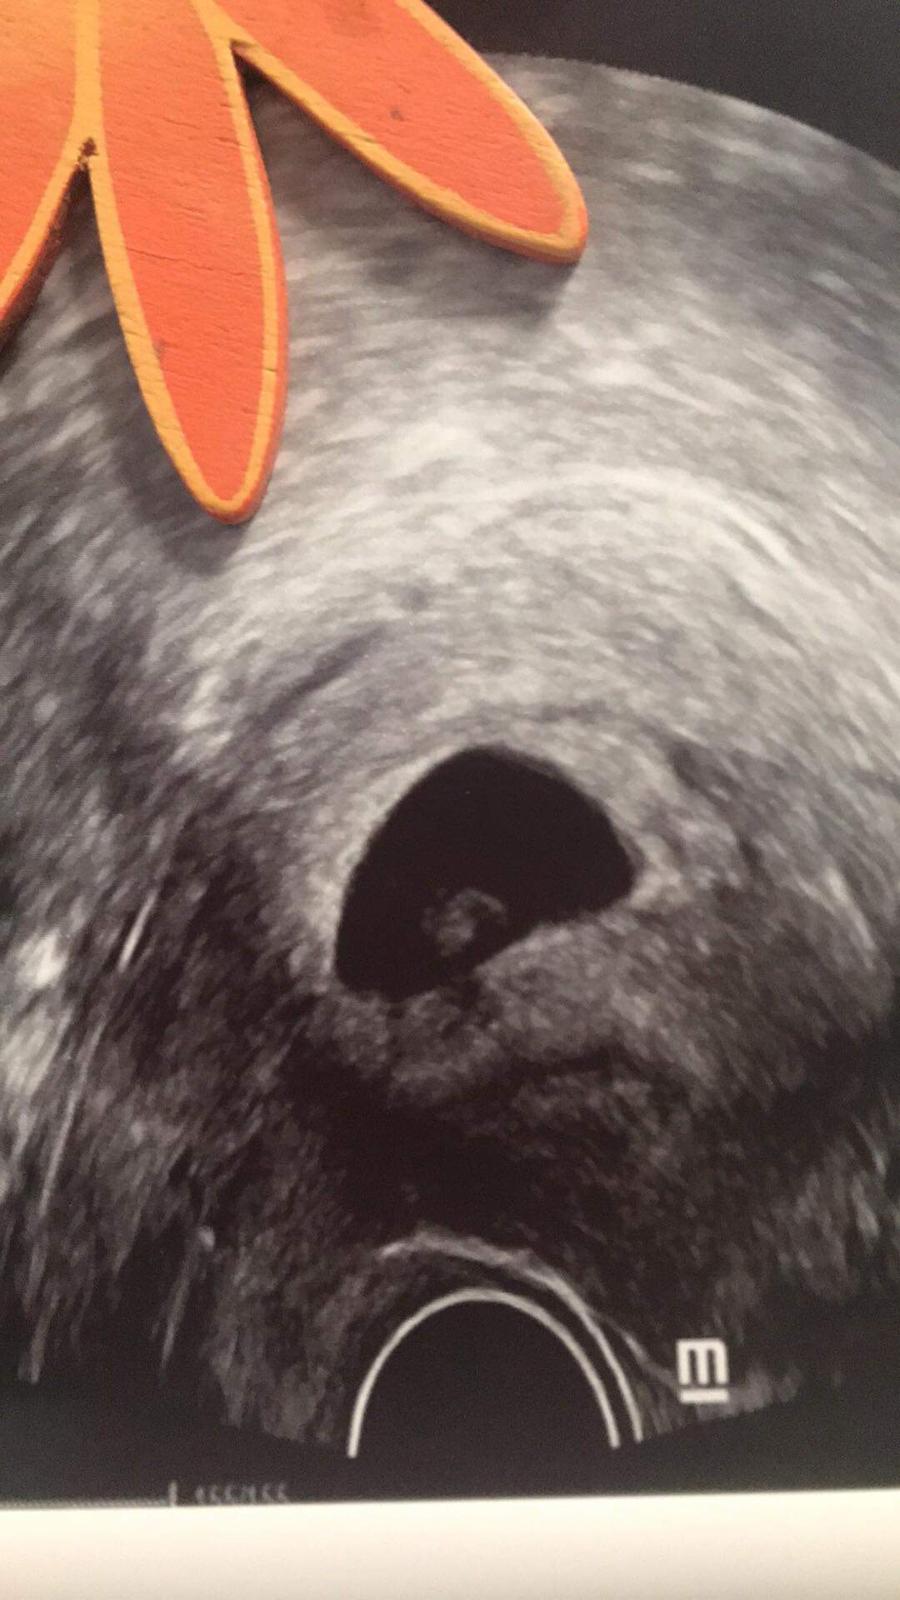

Ahoj🙂 dávám jen vědět že jste měli pravdu a opravdu jsem tehotna doktor to dnes z ultrazvuku potvrdil